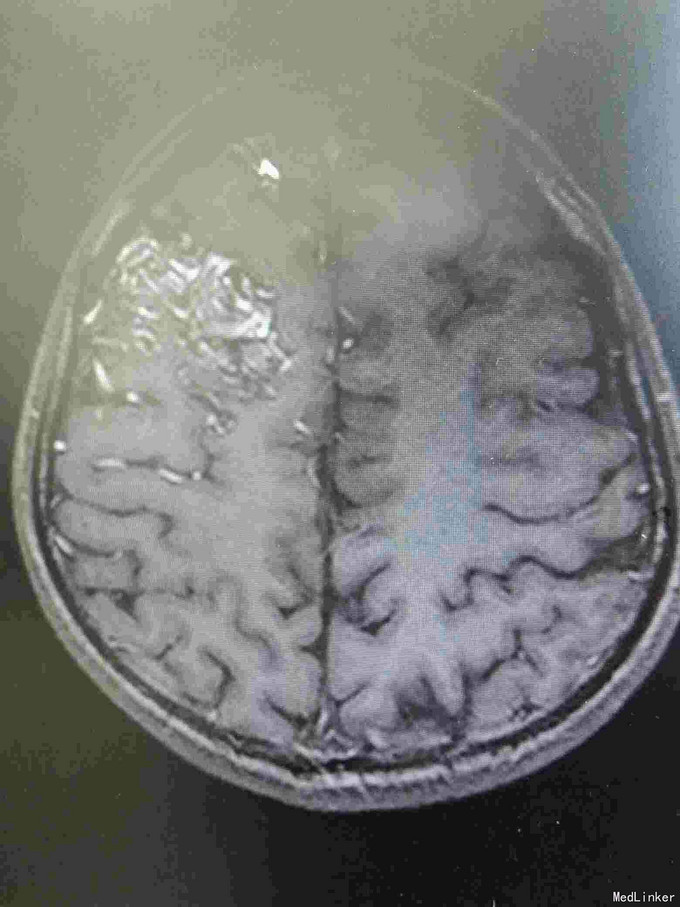

右额AVM

男,23岁。右额AVM。分次治疗。